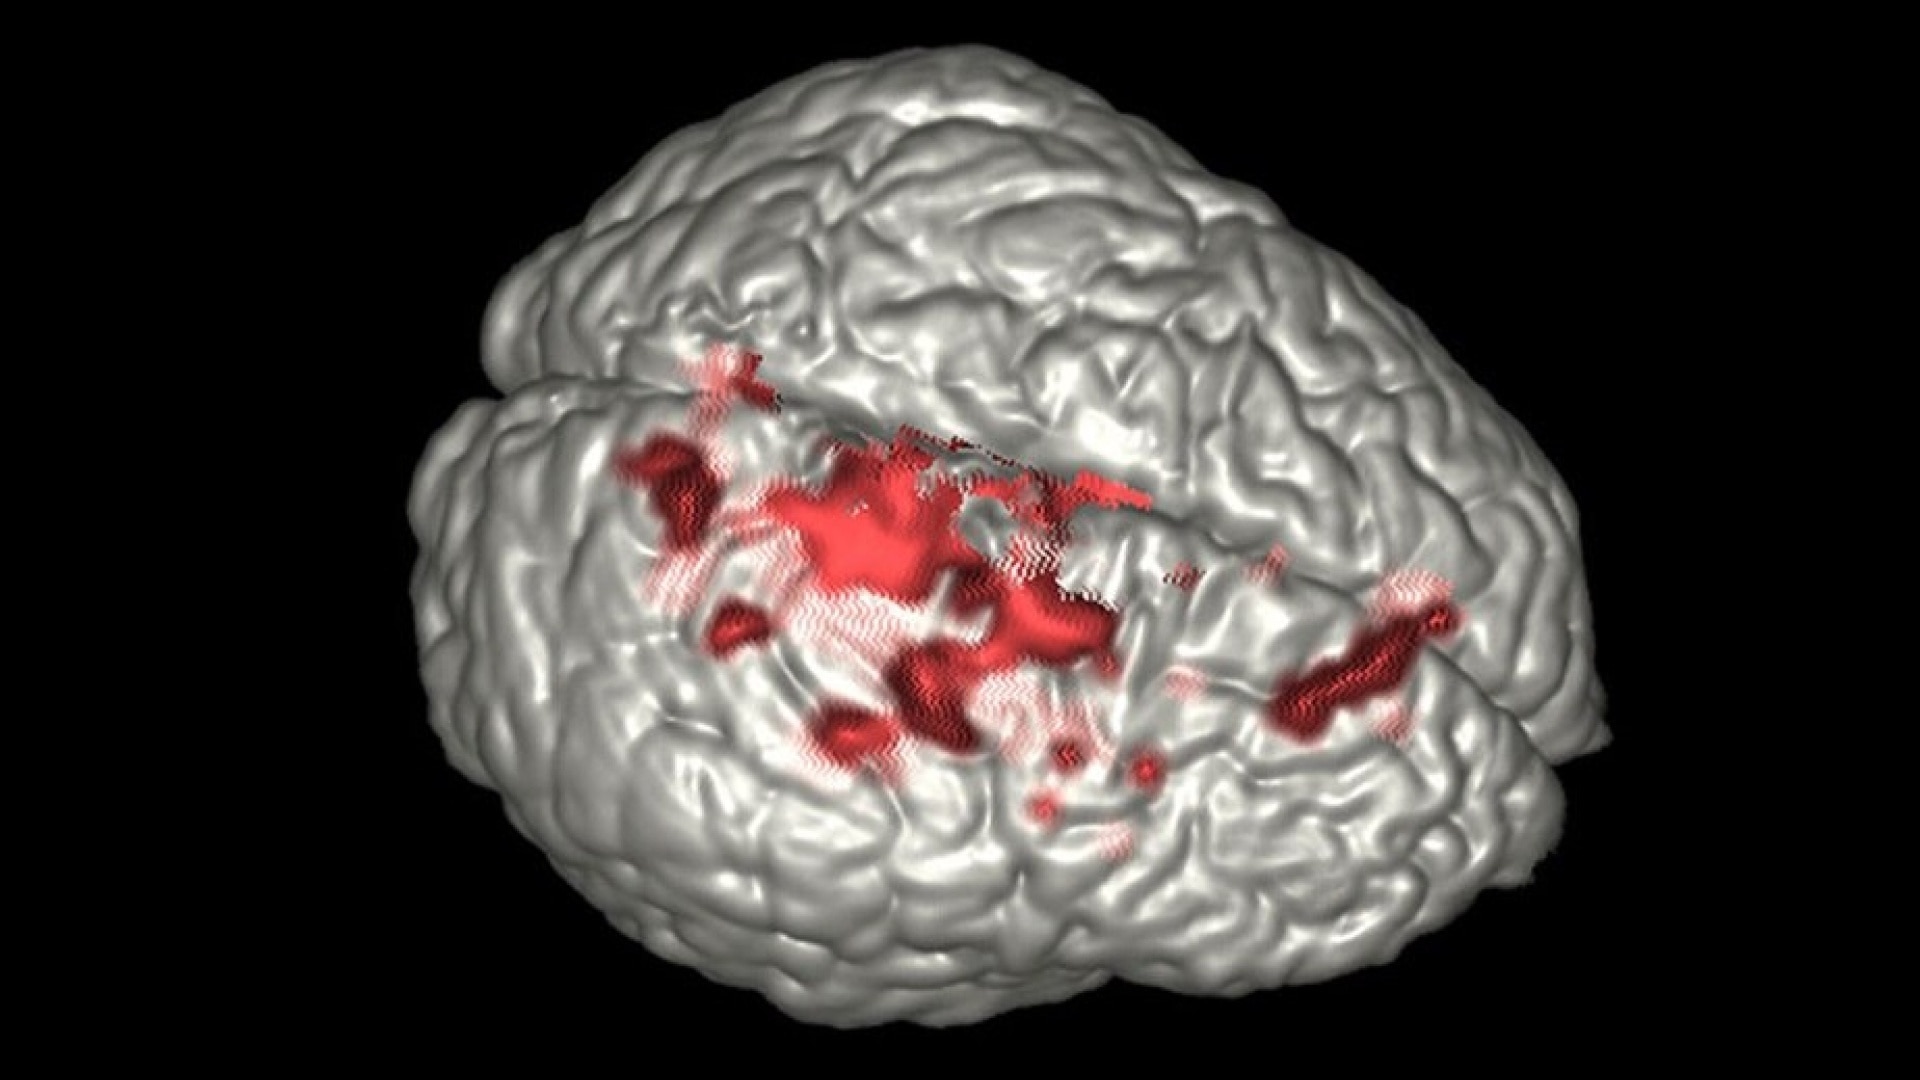

- Activation maps generated using Generalized Lineal Model (GLM) analysis

- Sophisticated visualization techniques that fuse analysis results with anatomical data

- Clear visualization with color activation maps and interactive thresholding